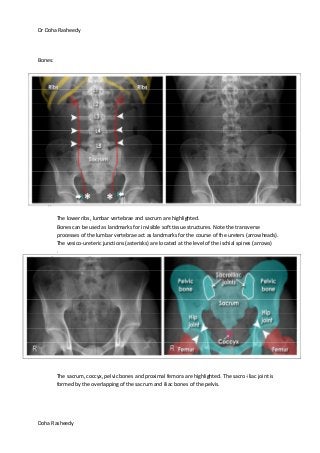

The lower ribs, lumbar vertebrae and sacrum are highlighted.

Bones can be used as landmarks for invisible soft tissue structures. Note the transverse

processes of the lumbar vertebrae act as landmarks for the course of the ureters (arrowheads).

The vesico-ureteric junctions (asterisks) are located at the level of the ischial spines (arrows)

The sacrum, coccyx, pelvic bones and proximal femora are highlighted. The sacro-iliac joint is

formed by the overlapping of the sacrum and iliac bones of the pelvis.